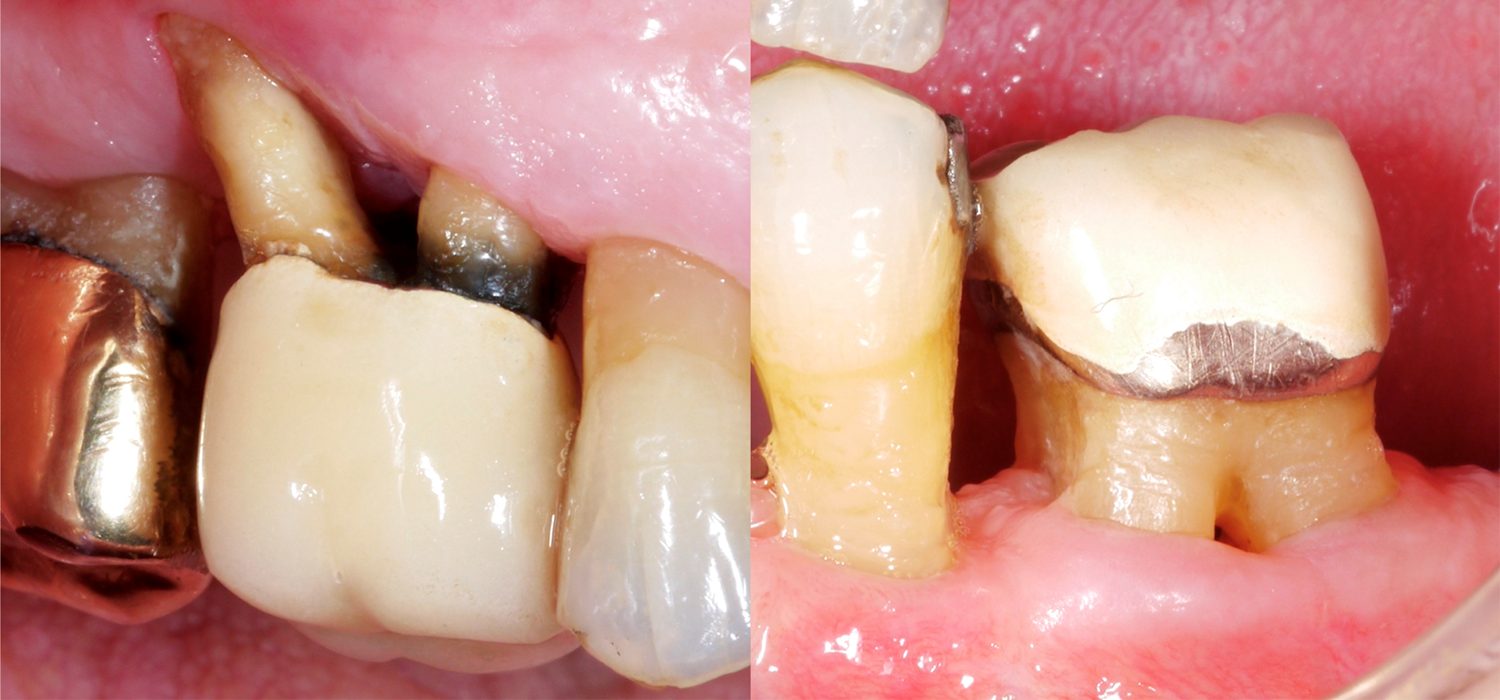

When it comes to teeth, those with multiple roots are, of course, often much more difficult to treat, especially if they present furcation defects. Why is the furcation area so challenging? In comparison to single-rooted teeth, access for mechanical cleaning of the root surface is much more difficult, the furcation entrance can often be very small/narrow, and there may also be further anatomical particularities, such as enamel projections.

A systematic review in 2016 (Nibali et al.) showed, for example, that teeth with a furcation defect are around twice as likely to have been extracted after 10–15 years of periodontal maintenance treatment. The risk of tooth loss also increases the higher the furcation defect grade; therefore, a molar with a through-and-through furcation defect (grade III) was approx. three times as likely to be lost than a molar with a grade I furcation defect.

A recently published study from Frankfurt (Eickholz 2021) specifically looked at teeth with a through-and-through furcation defect. They studied a total of 265 teeth with a through-and-through furcation defect in 160 patients; all patients had been receiving periodontal maintenance treatment for at least five years. We should take the following important points into account based on this data: